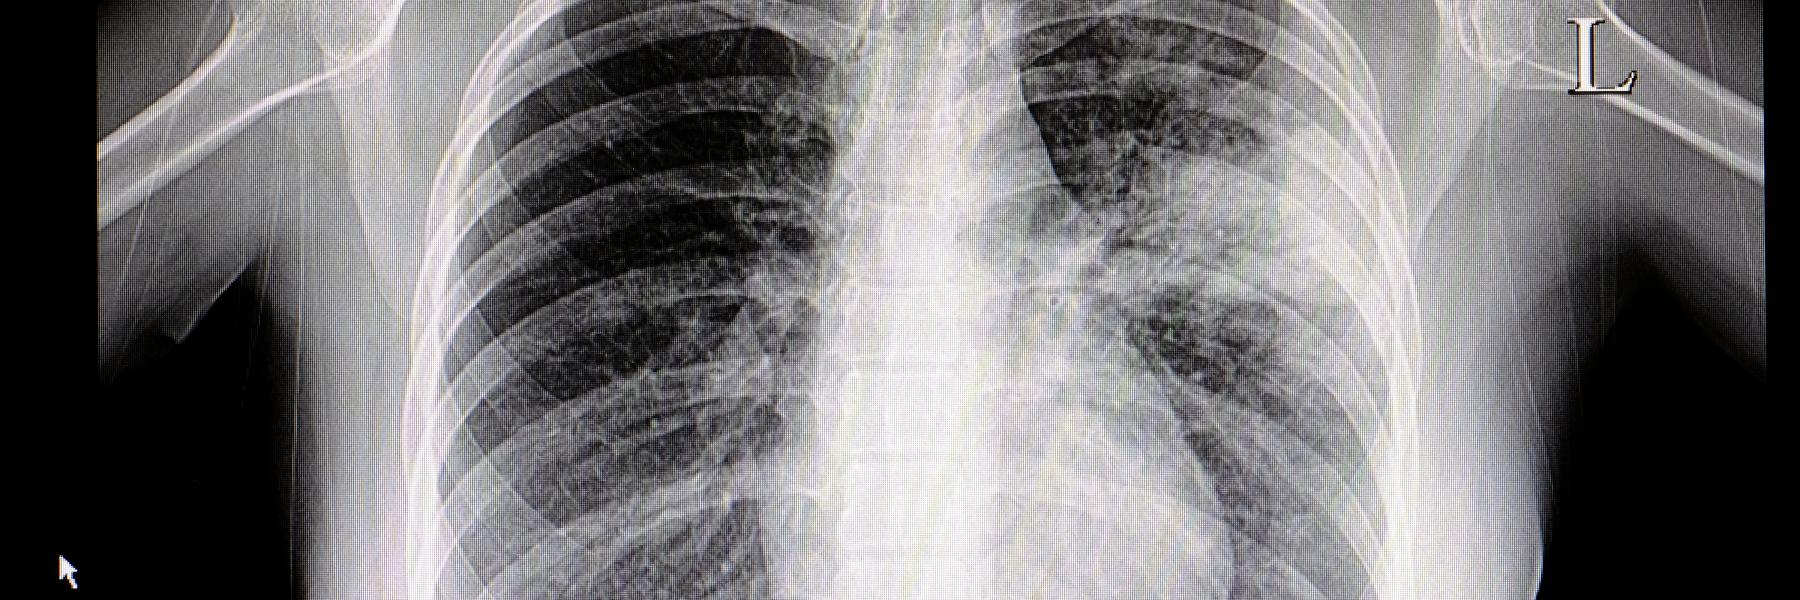

تليف الرئة من الأمراض الخطيرة التي قد تصيب الإنسان لما له من مضاعفات خطيرة، ويحدث نتيجة هذا المرض نقص فى كمية الأكسجين المتجهة إلى كافة أجهزة الجسم مما يسبب العديد من المضاعفات الخطيرة، مثل اضطراب فى ضربات القلب.

علاج مرض تليف الرئة: